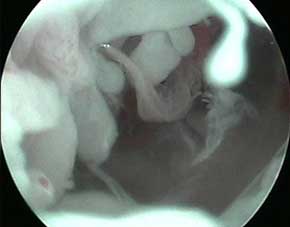

- 痛风检查

针刀镜技术针镜下可见痛风患者关节面散布痛风石